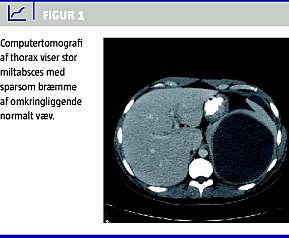

En 28-årig, tidligere rask, danskfødt mand med tyrkiske forældre blev set hos egen læge grundet intermitterende atraumatiske smerter i venstre skulder gennem flere måneder. Smerterne ændrede sig over tid til torakale smerter og siden til øvre abdominale smerter. Mere end et år efter symptomdebut fik patienten højfebrilia og blev indlagt akut. Ved indlæggelsen var patienten septisk, C-reaktivt protein var 241, der var leukocytose. En ultralydskanning af abdomen viste en cyste i milten. Behandling med albendazol, cefuroxim og metronidazol blev iværksat, og patienten blev overflyttet til en infektionsmedicinsk afdeling. Ved en computertomografi af abdomen fandt man en cyste/absces på 11 cm i diameter med en smal bræmme af normalt miltvæv omkring (Figur 1 ). En røntgenundersøgelse af thorax viste venstresidig pleural effusion med behov for drænage. Efter udelukkelse af amøbeabsces og ekinokokcyste med negativ indirect haemagglutination antibody (IHA)-titer og negative ekinokoktitre blev abscessen dræneret, og dyrkning viste Streptococcus anginosus . Abscessen blev initialt behandlet med antibiotika og drænage. Abscessen gendannedes, og nye kaviteter i milten tilkom. Disse blev også dræneret, men uden kurativ effekt. Patienten blev slutteligt splenektomeret efter forudgående pneumokokvaccination.